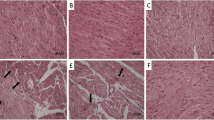

On the other side, Fig. 2 showed the normal architecture of the renal cortex, renal corpuscle, glomerulus, proximal convoluted tubules, and distal convoluted tubules of rats from the control, LP, and NAC groups. In contrast, CP-intoxicated rats exhibited severe nephrotic lesions associated with marked degenerative changes within the renal tubular epithelial lining, congested inter-renal blood vessels, hydropic degeneration, pyknotic nuclei in epithelial cells, and hyaline cast materials in the lumen of most tubules. Treatment with LP, NAC, or their combination prevented the histopathological kidney changes induced by CP.

Histopathological changes in kidney sections. (a)–(c) Normal architecture of the renal cortex, renal corpuscle (arrow), glomerulus (G), proximal convoluted tubules (P), and distal convoluted tubules (D) in the control (a), LP (1b), and NAC (d) groups. (d) CP-induced severe degenerative changes 1in the renal tubule epithelial lining (f), congested inter-renal blood vessels (I), hydropic degeneration (thin arrow), and pycnotic nuclei of epithelial cells (thick arrow). (e) CP-induced loss of normal architecture in the renal tubules, with hyaline cast materials in the lumen of most tubules (thick arrows), degranulated cytoplasm in some epithelial cells (d), and desquamated cells (thin arrow). (f) Histological changes in the kidney in the LP + CP group. Moderate effects in the renal tubules and degenerated and sloughed epithelial cells (thick arrow). (g) Histological changes in the kidney in the NAC + CP group. Moderate effects include congested inter-renal blood vessels (C), hyaline cast materials in the lumen of some tubules (h), and necrosis in some epithelial cells (e). (h) Histological changes in the kidney in the LP + NAC + CP group. Mild effects include proteinaceous materials in the lumen of some tubules (thick arrows). Scale bar = 50 μm.